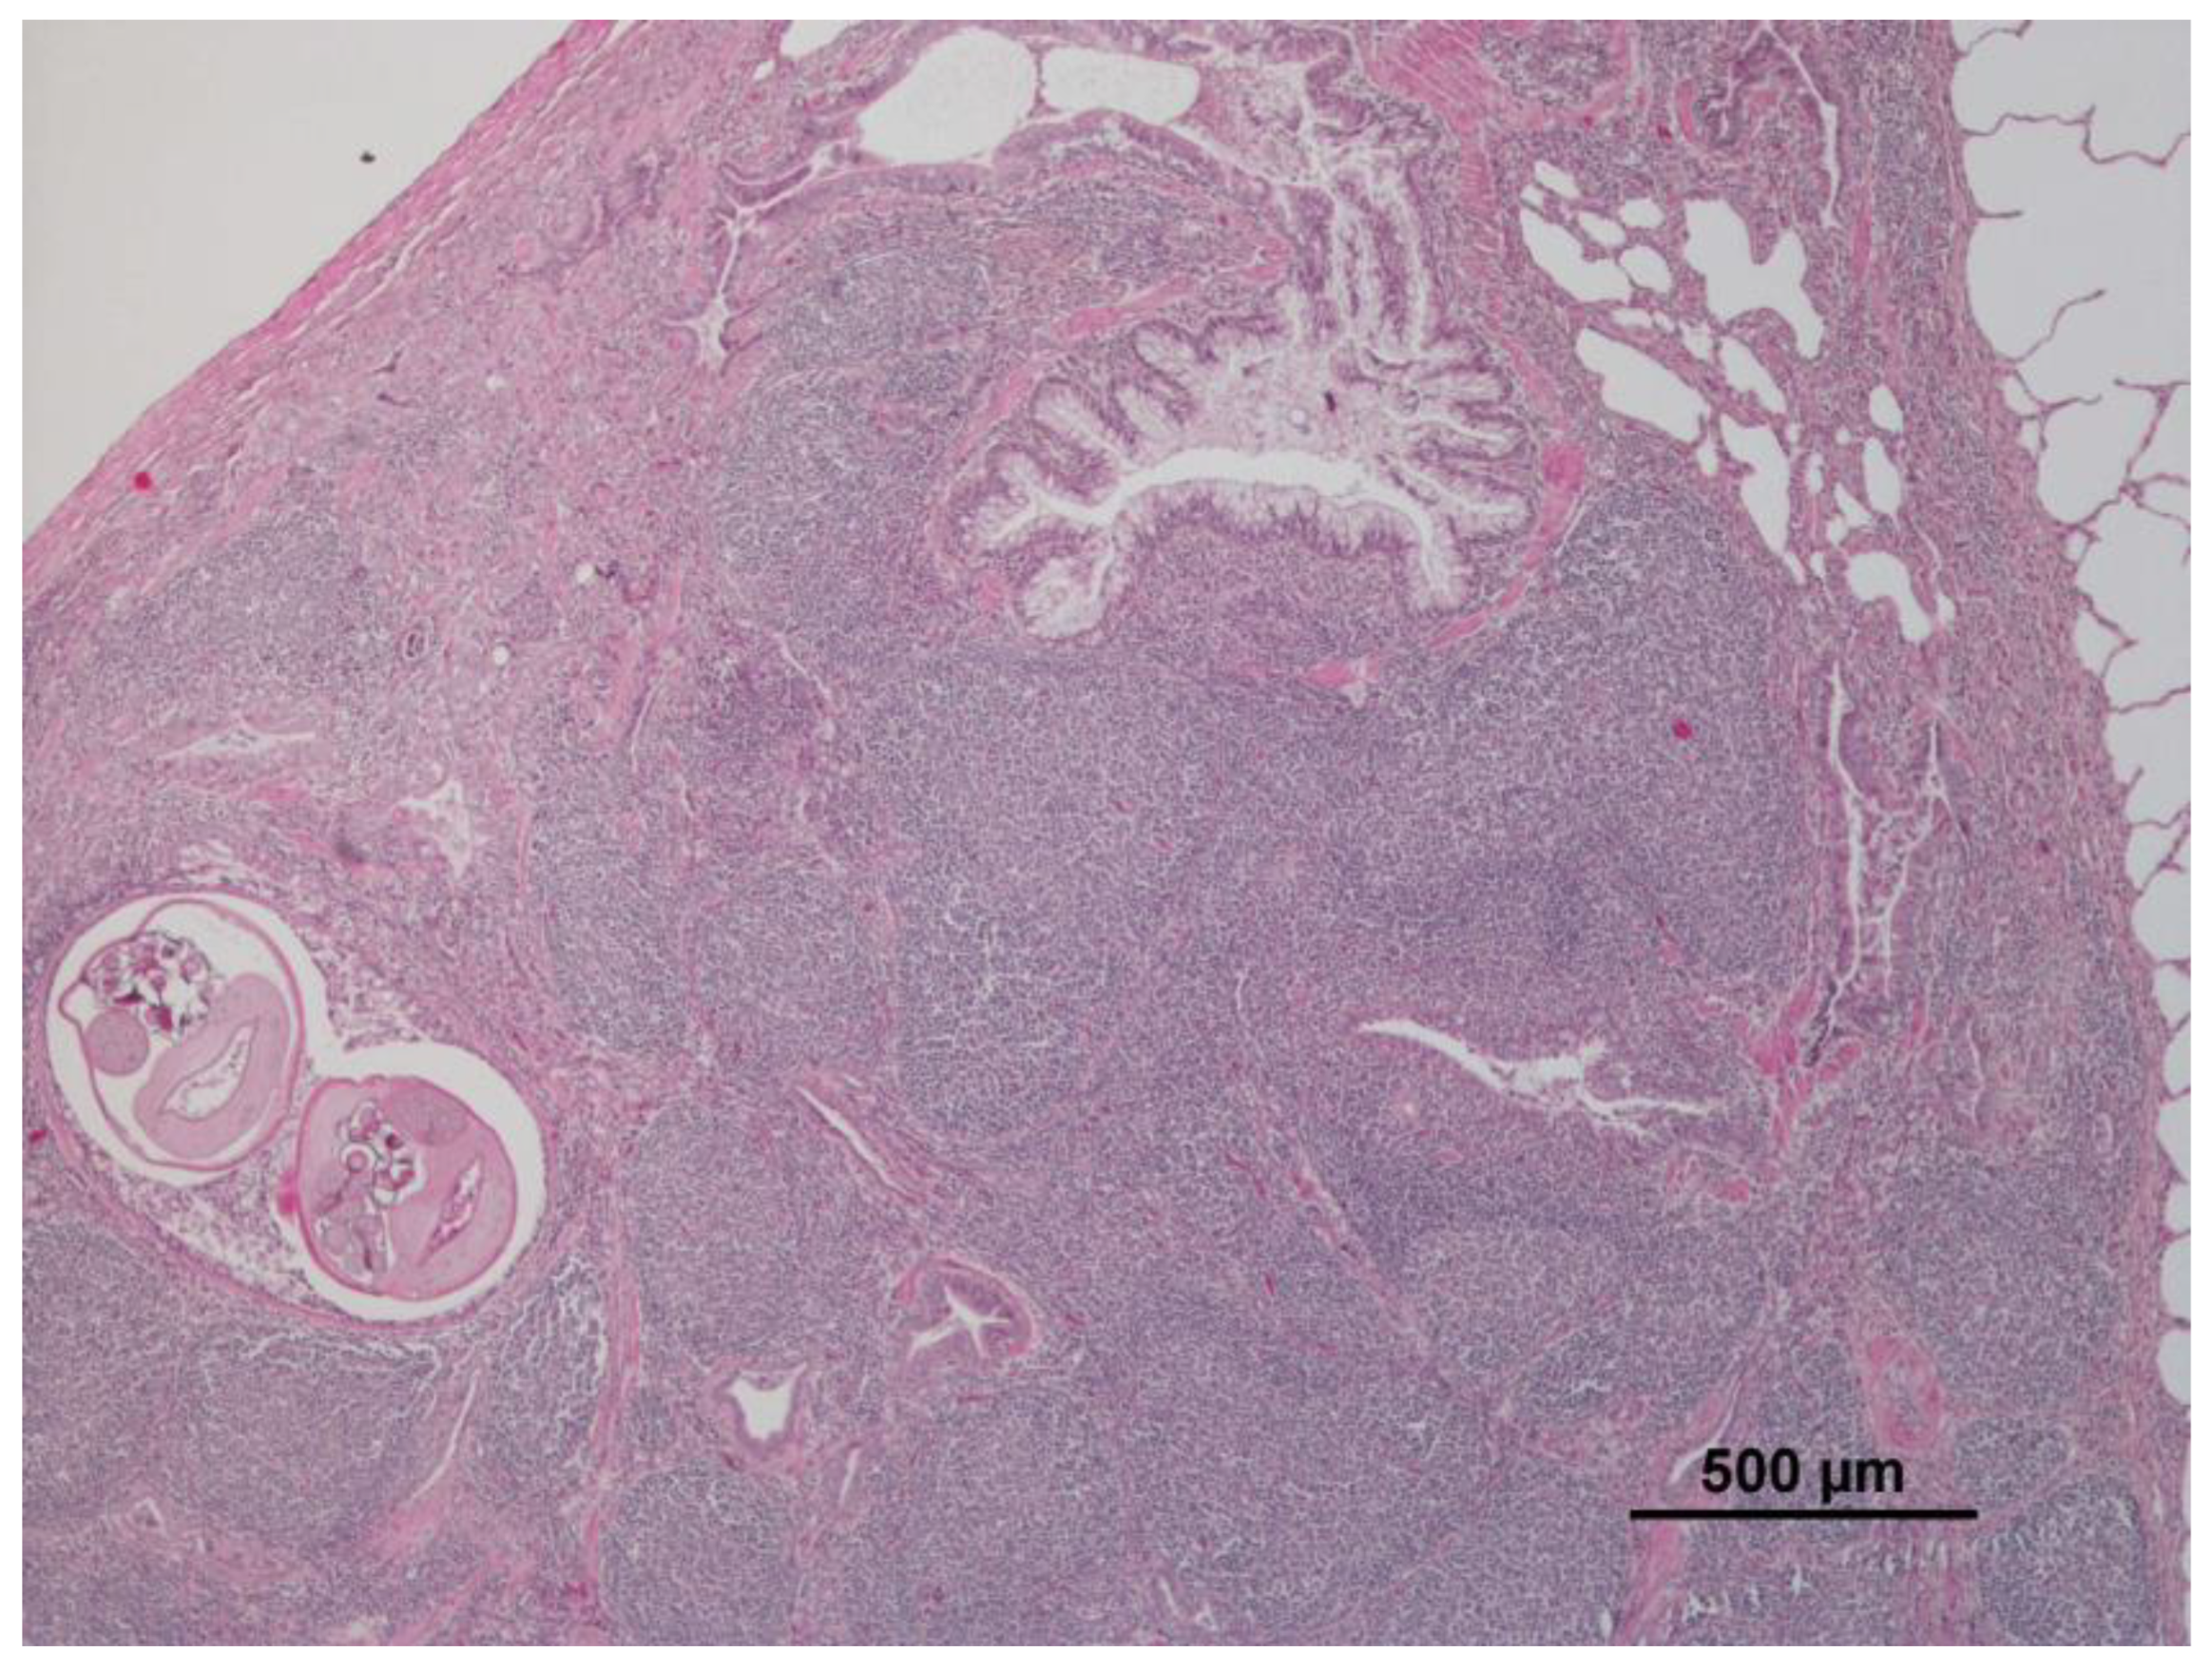

3.1. Lung

| Lymphoid hyperplasia | 26 | 36.1 | Cellular changes: cell swelling; hydropic change; vacuolar change | 24 | 33.3 | Non-purulent nephritis | 16 | 22.2 |

| Verminous bronchitis | 25 | 34.7 | panlobular | 8 | 11.1 | Renal steatosis | 2 | 2.8 |

| Atelectasis | 14 | 19.4 | diffuse/not specified | 15 | 20.8 | Chronic interstitial nephritis | 2 | 2.8 |